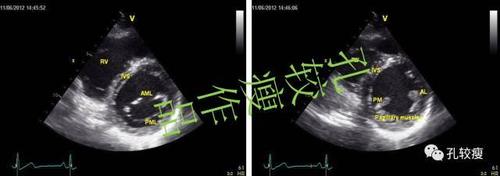

心尖四腔观变异切面

心尖四腔心超声图解